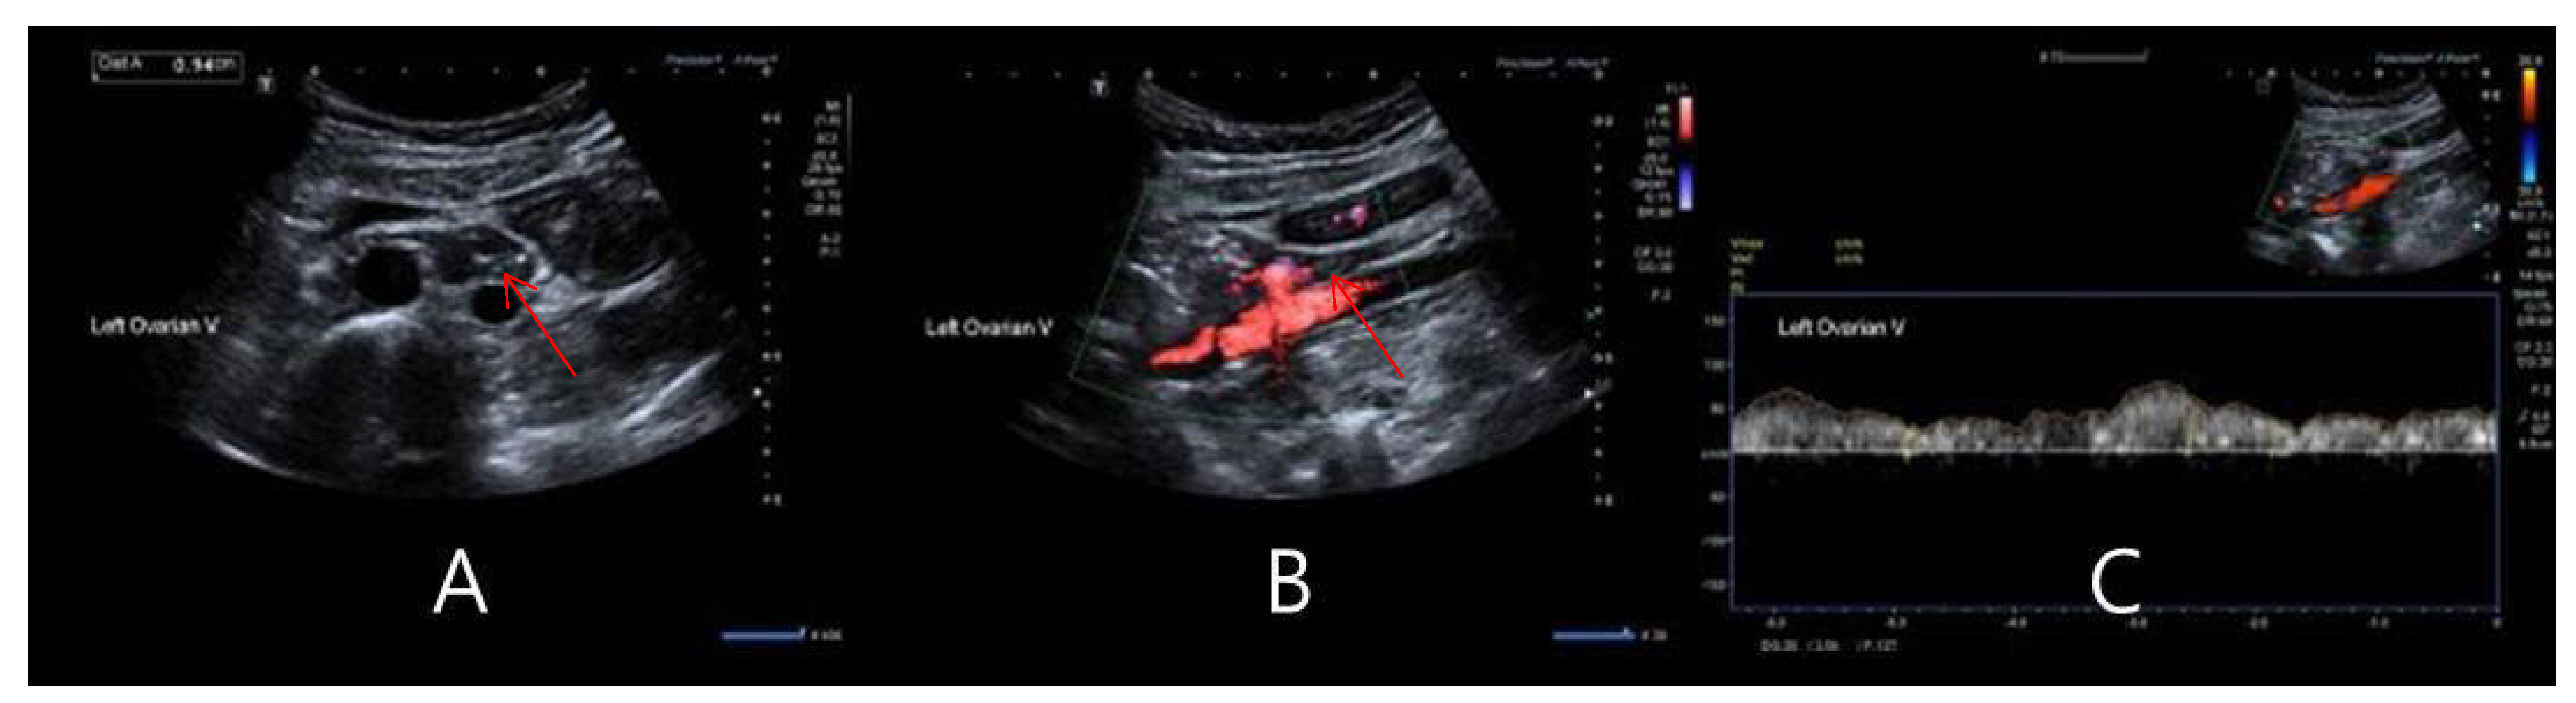

2.3. Gonadal Vein DUS